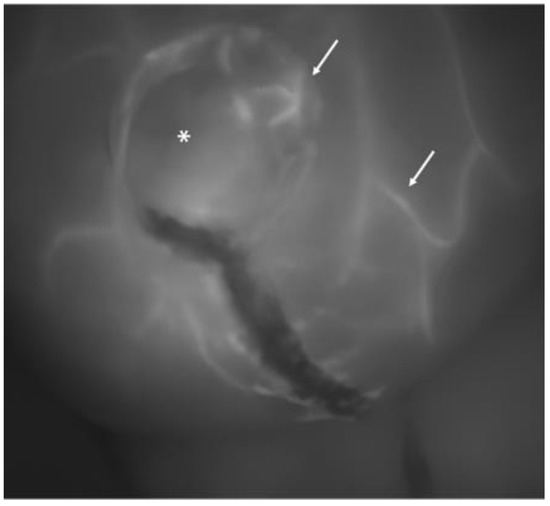

When the contrast permeated the skin layer through the capillary system, the grayscaled screen showed the radially extending pattern of vascularization from the perforator vessels (Figure 1 and Figure 2).

Another image of a breast at the completion of the procedure: the asterisk indicates a skin perforator vessel from which several small tangential vessels branch out (white arrows). This pattern is characteristic of a well-perfused skin flap.